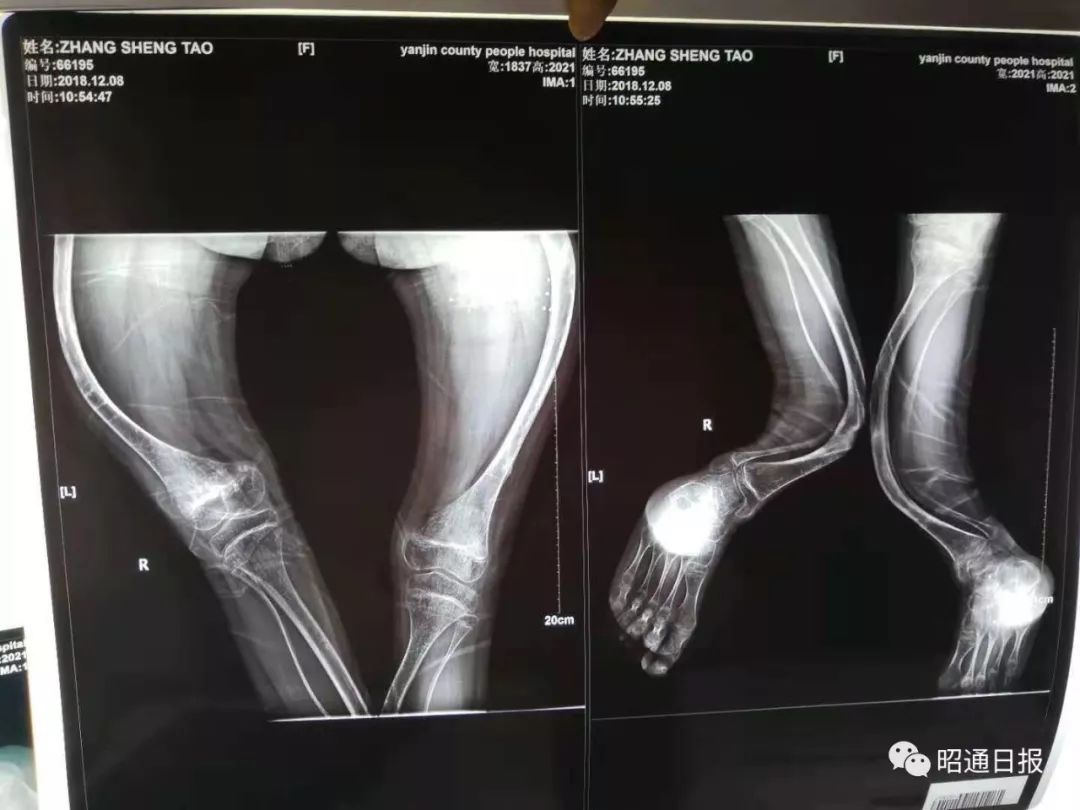

12年骨折30多次云南 瓷娃娃 坚强得让人心疼 都市时报 微信公众号文章阅读 Wemp

正骨精湛医术 让他的手又变长了 骨折术后骨不连怎么办 福建中医药大学附属泉州市正骨医院